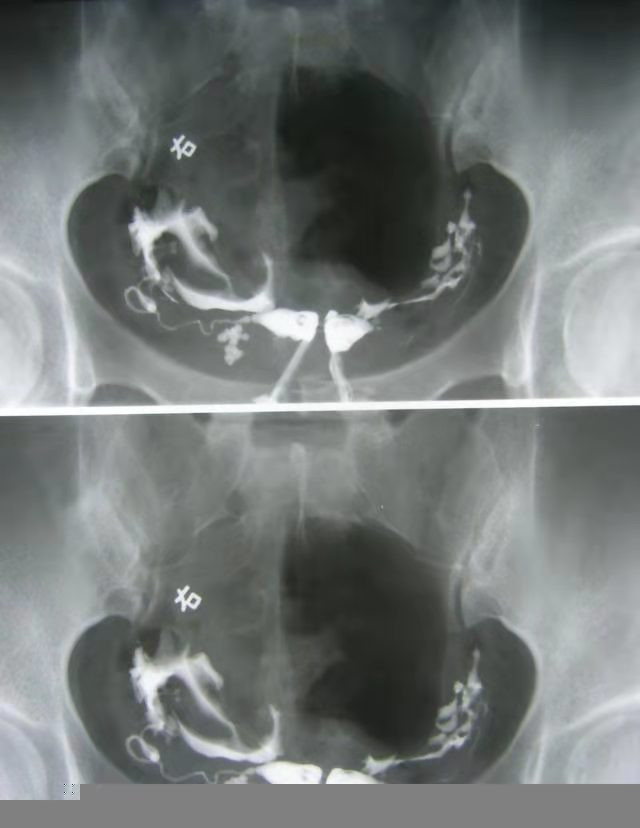

王女士,21岁,因 *生活性**后会阴及下腹部疼痛 至我院妇产科就诊,检查发现 阴道为不全纵膈,距离阴道口1.5cm,双宫颈,双子宫 。

千真万确 ,有人就有双阴道、双子宫!我还记得几年前台湾就有一则新闻报道,一名女大学生意外怀孕,前往妇产科就医时发现竟然是双阴道、双子宫患者,该女学生距阴道开口1/3处有一隔膜组织将阴道一分为二。当时接诊的医生说该情况的发生率仅为 1/(5000-10000) ,容易流产早产,需规律产检。

而当各种因素,导致 正常生殖道形成受阻 时,就会出现如 阴道横隔 、 阴道纵隔 、 阴道闭锁 和 宫颈闭锁 等情况。我们今天所说的 双阴道 就是生殖道畸形中 较为常见 的一种,即 由于阴道内隔纵向附着在阴道内正中,将阴道一分为二的现象 。